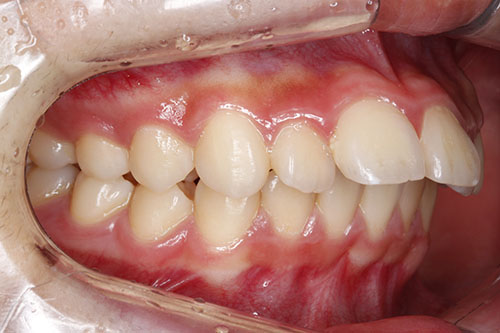

우선 저는 성인이구요(20대 후반) 사진에서 보이다시피 아래쪽에 유치가 두개 있는 상태입니다. 이걸 임플란트를 할지 교정으로 이를 밀어버릴지 고민이예요. 임플란트로만 처리한다면 더 오래 유치를 가지고 있어도 ...